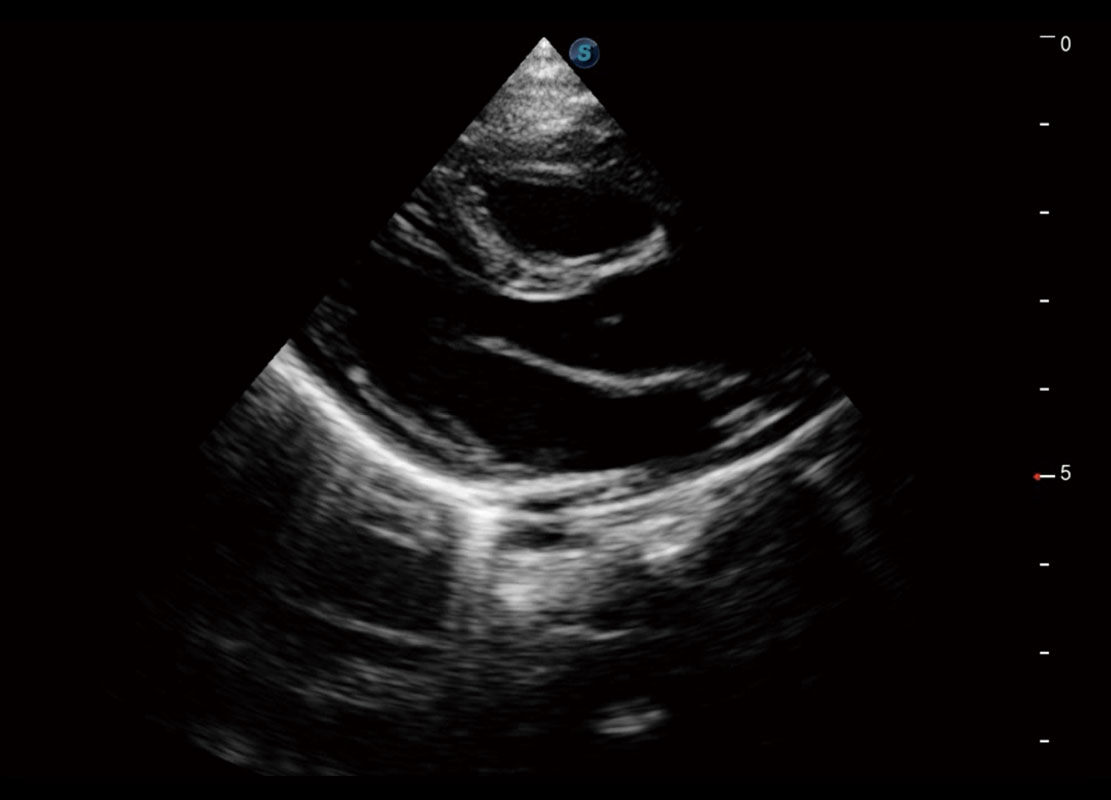

新生兒心臟

P60搭載寬頻帶線(xiàn)陣探頭、寬景成像、彈性成像技術(shù),為您提供乳腺應(yīng)用方案。P60支持高頻相控陣探頭、線(xiàn)陣探頭、腹部高頻探頭、腹部微凸探頭等,豐富的探頭群搭載敏感的彩色血流成像,適用于新生兒多種臟器檢測(cè)要求,滿(mǎn)足新生兒篩查需求。